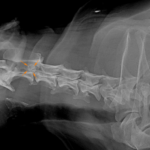

体の何処かを痛がるとの事でダックスさんがかかりつけ医を受診したところ、椎間板ヘルニアではないか?との頃で精査のため来院されました。エックス線検査とMRIでC2~C3に脊髄圧迫病変が確認されました。Ventral Slotで脊柱管内に逸脱した椎間板物質を摘除しました。速やかに除痛効果が現れています。